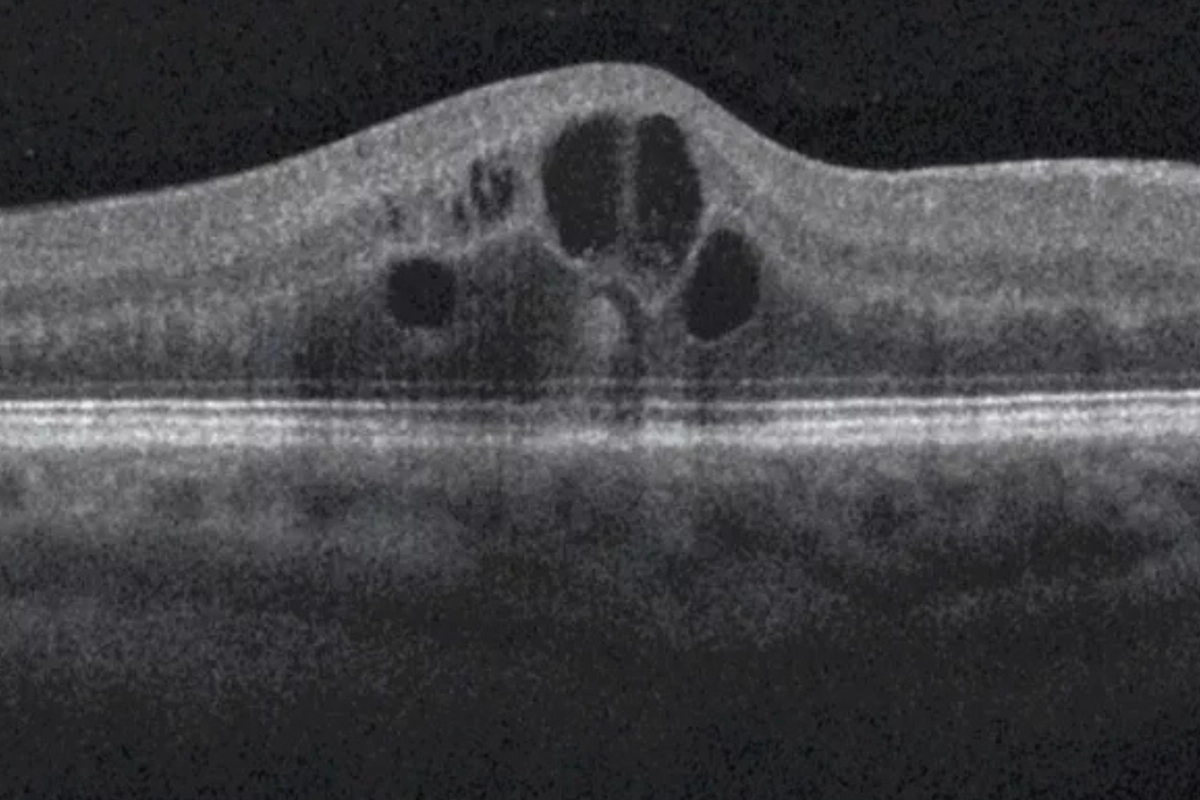

The gold standard for detecting diabetic macular edema. OCT produces a precise, cross-sectional map of your macula — measuring retinal thickness, identifying fluid accumulation, and detecting structural changes that are completely invisible during a standard exam. It's how we catch DME early, before it causes permanent central vision loss.

Diabetic macular edema occurs when fluid leaks from damaged retinal blood vessels into the macula — the central part of the retina responsible for sharp, detailed vision. The macula swells, causing blurry or distorted central vision. DME can develop at any stage of diabetic retinopathy and requires prompt evaluation and coordinated care with a retina specialist.